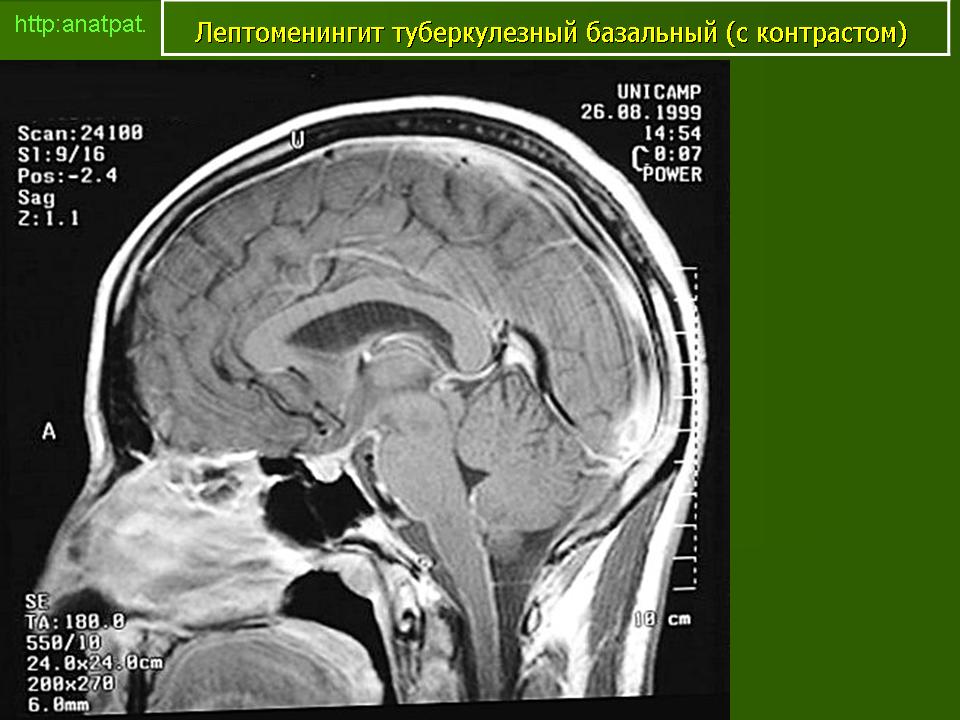

Менингеальный больной туберкулёзом на фоне ВИЧ.

anatpat.unicamp